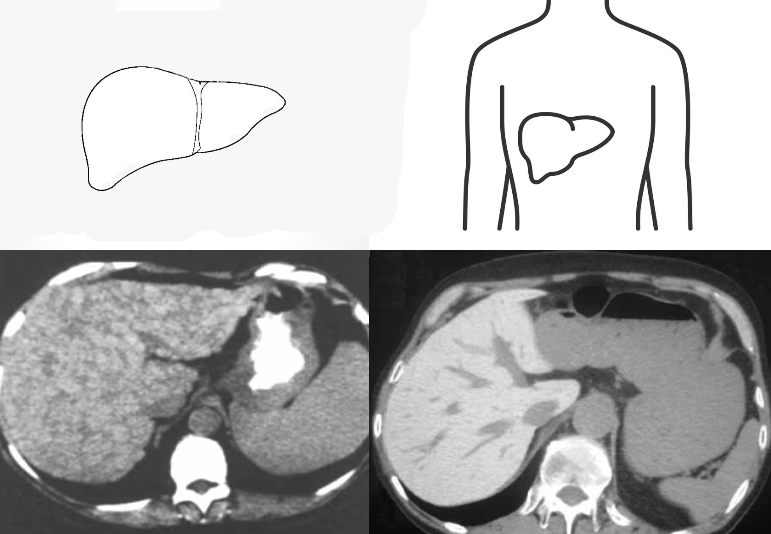

Симптом «белой печени»

А вы знали, что при циррозе печени на КТ-изображениях можно 👀увидеть такой симптом, как «белой печени». Это происходит за счет избыточного накопления в печени веществ с высокими показателями ослабления рентгеновского излучения — гемосидерина в узлах регенерации. А это, в свою очередь, ведет к значительному повышению плотности органа. Также у пациентов, принимающих кордарон (амиодарон), может повышаться плотность печени.